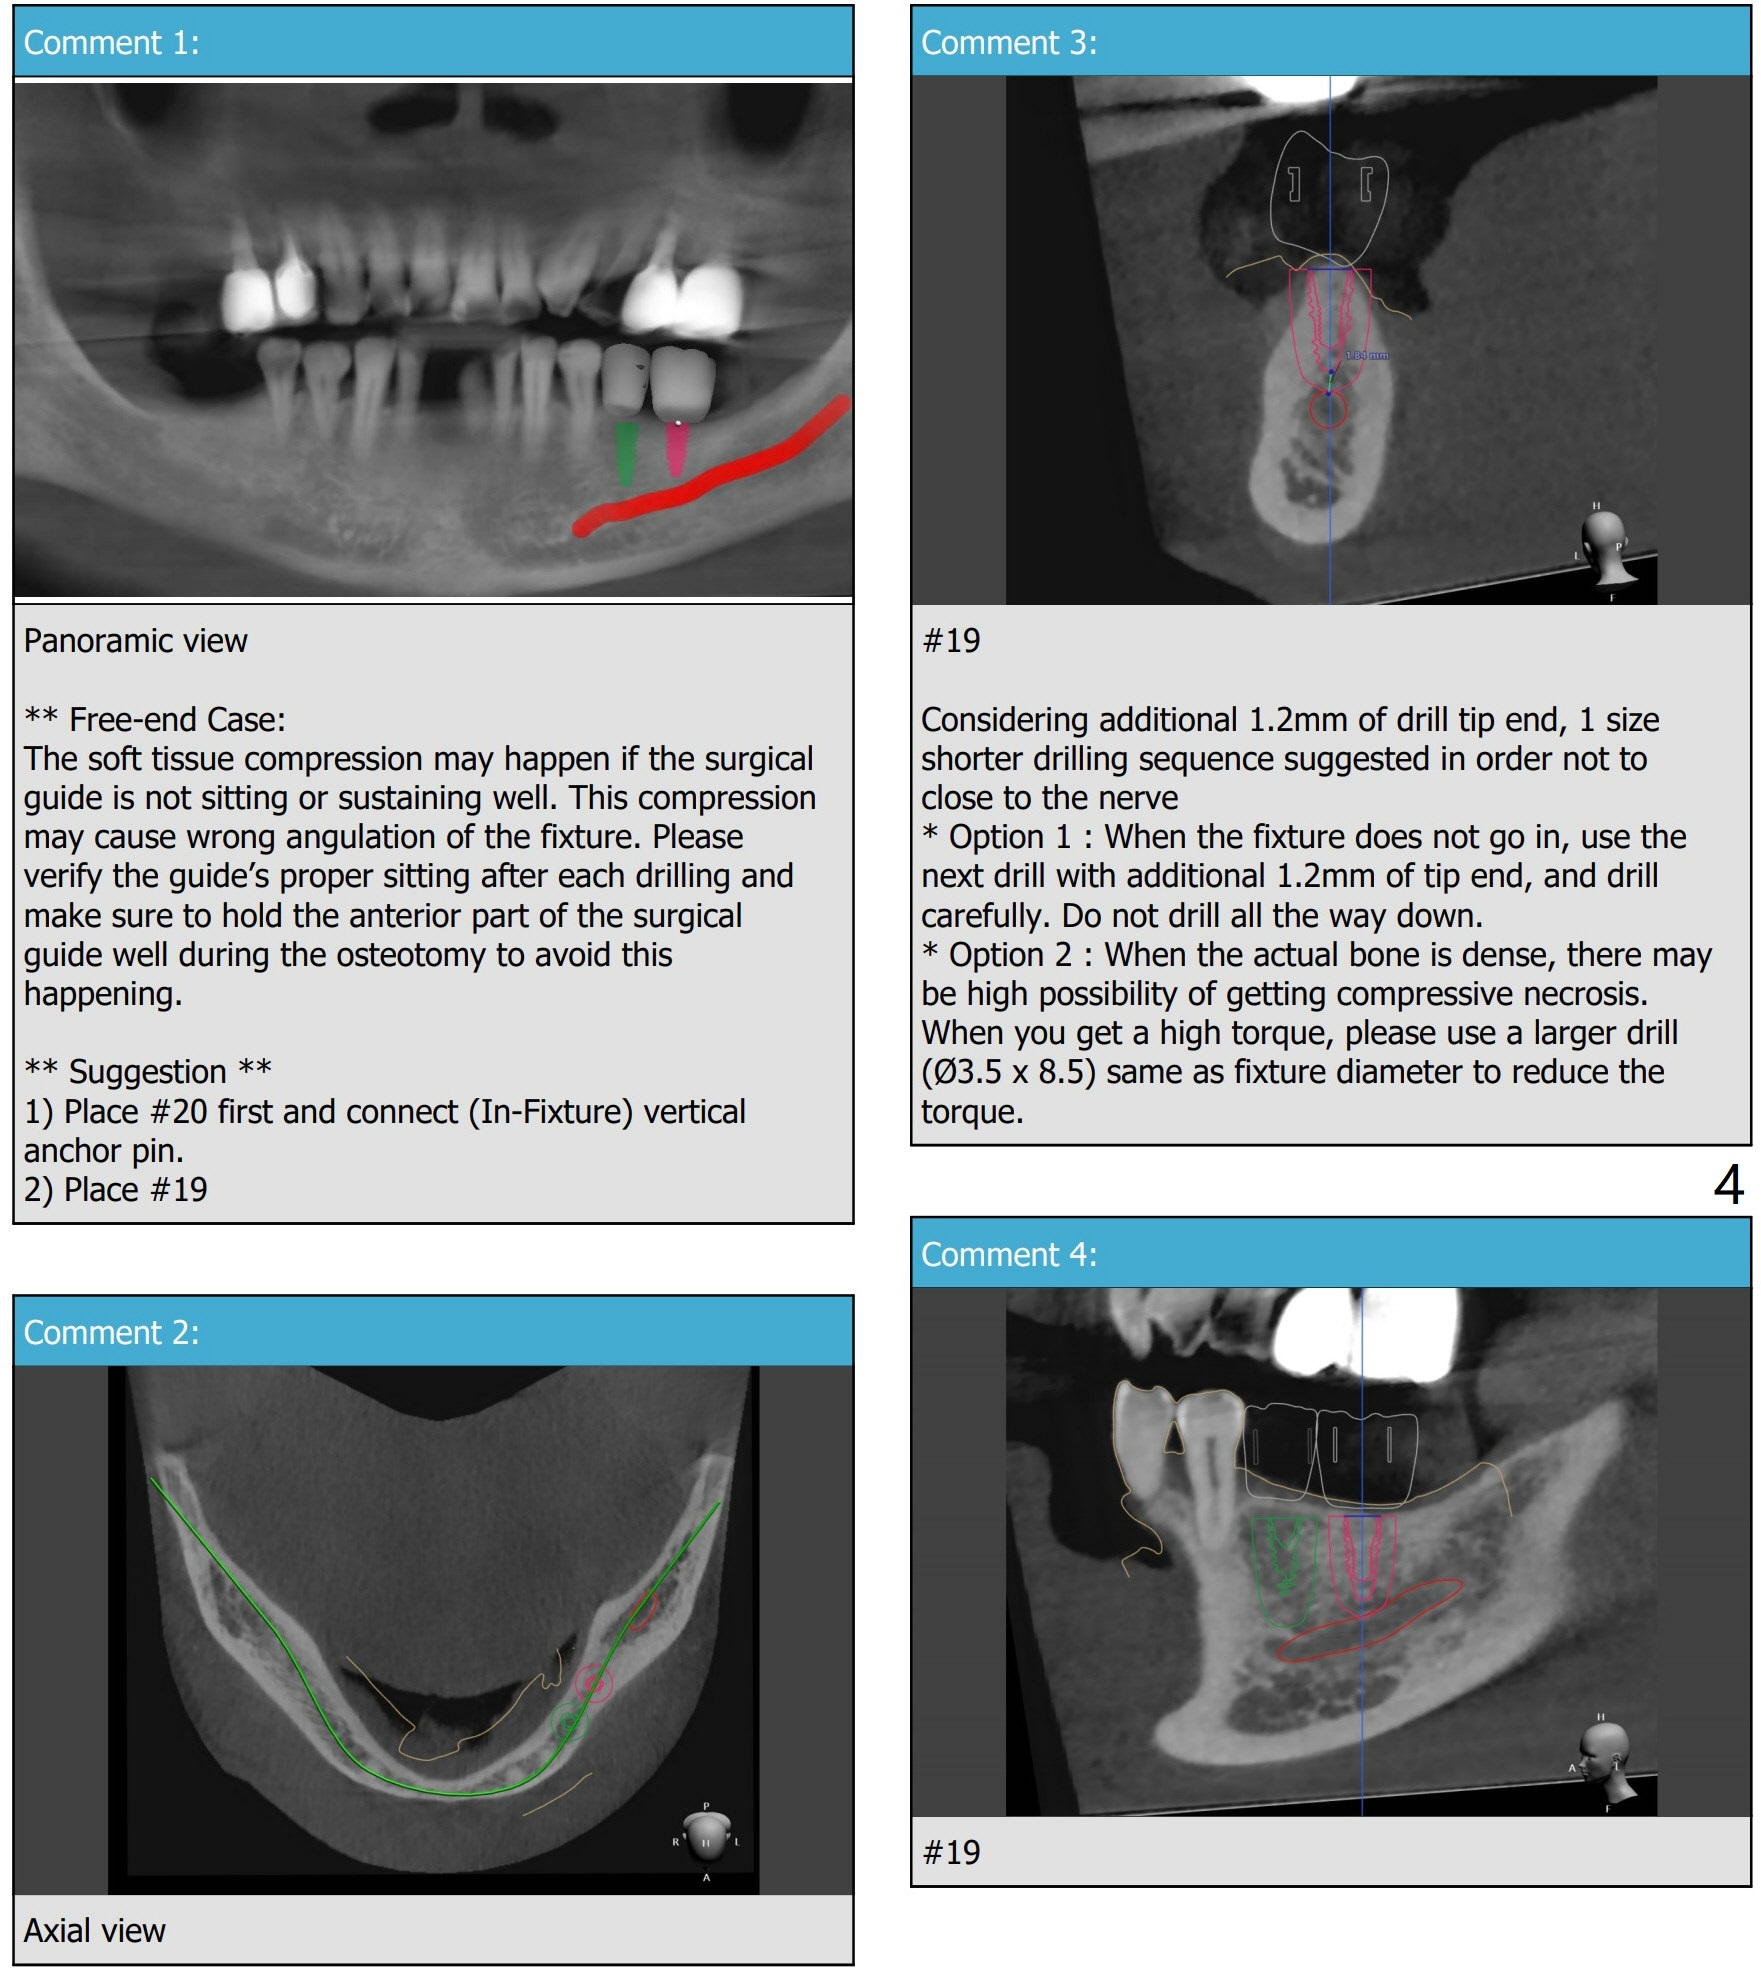

1-P, 2-P, Guide and Free Hand

PRFx1.  Underprep in depth for primary stability

Return to No Deviation  No Caries Torque